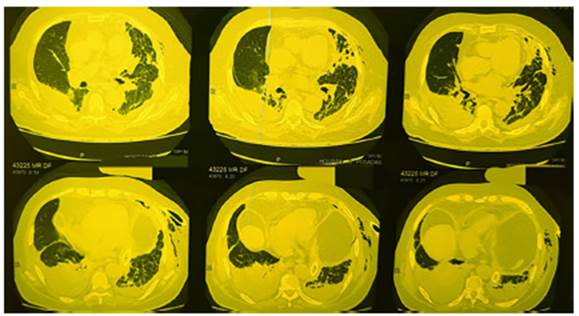

initiated. Chest CT scan: left-sided hydropneumothorax with pleural drainage

tube, right-sided loculated pleuÂral effusion with organized appearance, and

bilateral pulmonary consolidations, predominantly on the right side (Fig. 1).